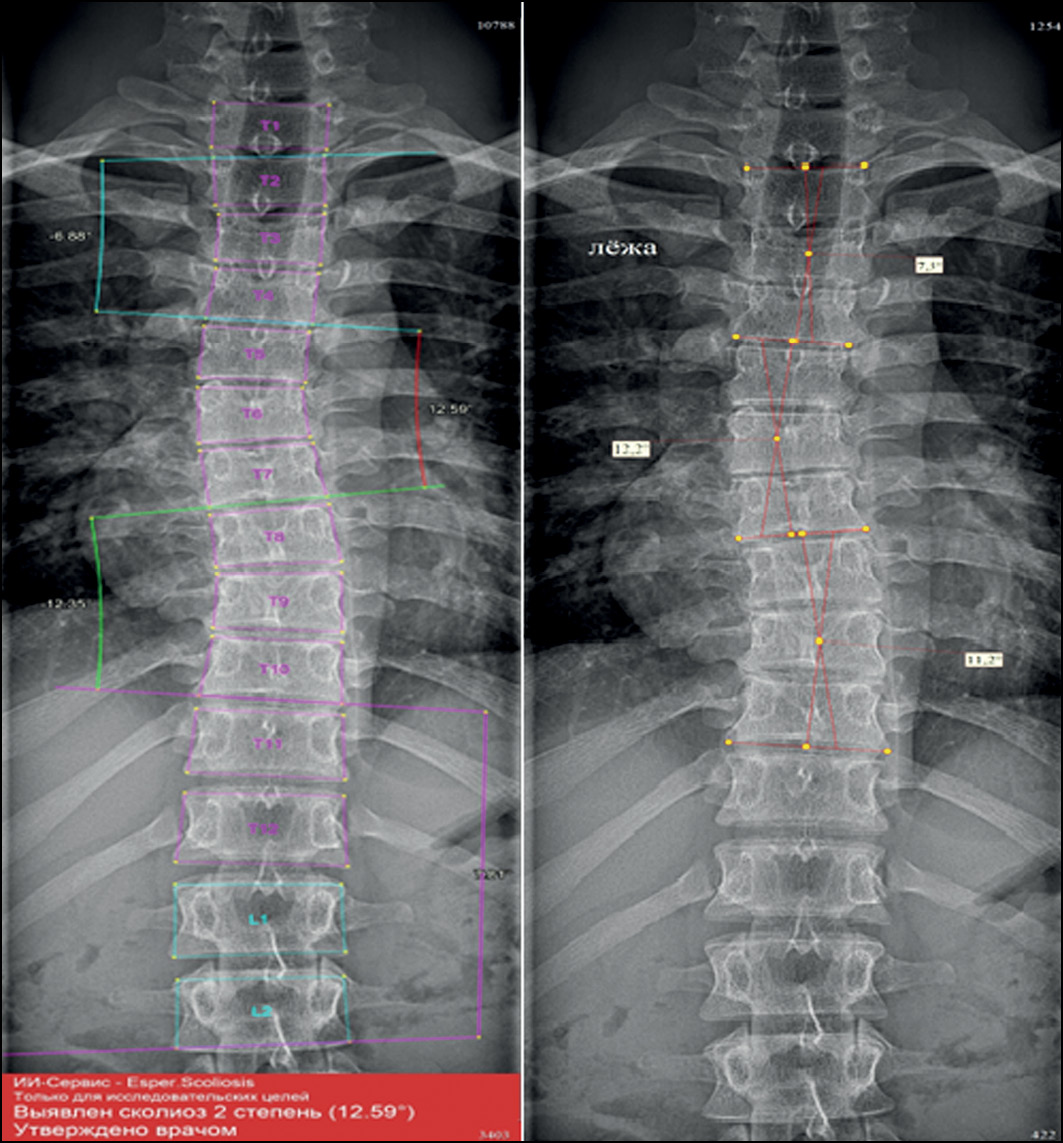

The bulk of this work was performed in a hospital where adolescents are screened for scoliosis, as part of multiple examinations for medical commissions, to determine whether adolescents match the criteria for army enlistment. Thus, radiographs in test set 1 and test set 2 were divided according to the severity classification included in Federal Law No. 565, where any small curves with angles <10° are considered grade 1 scoliosis [16]. The new automatic system for evaluating scoliosis on digital radiographs can help radiologists to define the scoliosis grade and measure the curve’s angle, particularly in situations such as screening for scoliosis and at times of heavy workload in outpatient clinics. In these situations, radiologists can use the program as an objective tool, increasing the accuracy of scoliosis evaluation on frontal radiographs because the interobserver variability can be avoided if radiologists use the same instrument. Moreover, it can significantly save the radiologist’s time. In addition, Cobb’s angles measured by the system were acceptable, with no significant clinical variability in most of the evaluated curves. Fig. 4 shows an example of how the system works.

In addition, when using the program, the radiologist can change vertebral markings made by the system automatically. This is very essential to overcome any errors in vertebral markings that can cause a false final result. Further analysis of the results showed that the inaccurate marking of vertebral bodies and their borders predominantly led to less accurate results of angle measurement and scoliosis grade definition. This was mainly seen when evaluating scoliosis in poor-quality images and CXR images. The borders of the midthoracic vertebrae in CXR images usually are not seen posterior to the mediastinum. Multiple normal CXR images (grade 0, defined by the radiologist) were recognized by the system as grade 1 scoliosis because of detecting an FP curve (proximal or midthoracic curve) (Fig. 5). Other common error was also seen in marking the borders of L5 vertebral body (Fig. 6). The adjacent bony structures (adjacent sacrum and iliac bones) limit the definition of L5 borders, particularly its lower endplate.

Regarding errors in evaluating images with group 0 scoliosis, most of the measurements by the AI system resulted in angles with >5° but very close to it. However, such minimal variability in measurements between the system and the radiologist led to a change in the grade from 0 to 1 (Fig. 7). The majority of such angles (70%) were found in the range of 5°–6°, as shown in the pie chart (Fig. 8).

Fig. 7. Errors of the system in evaluating images with grade 0 scoliosis. Cobb’s angles measured by the radiologist (left) and the AI system (right). Measurement variability is not significant (1.4°); however, the scoliosis grade is 0 by the doctor and 1 by the system.